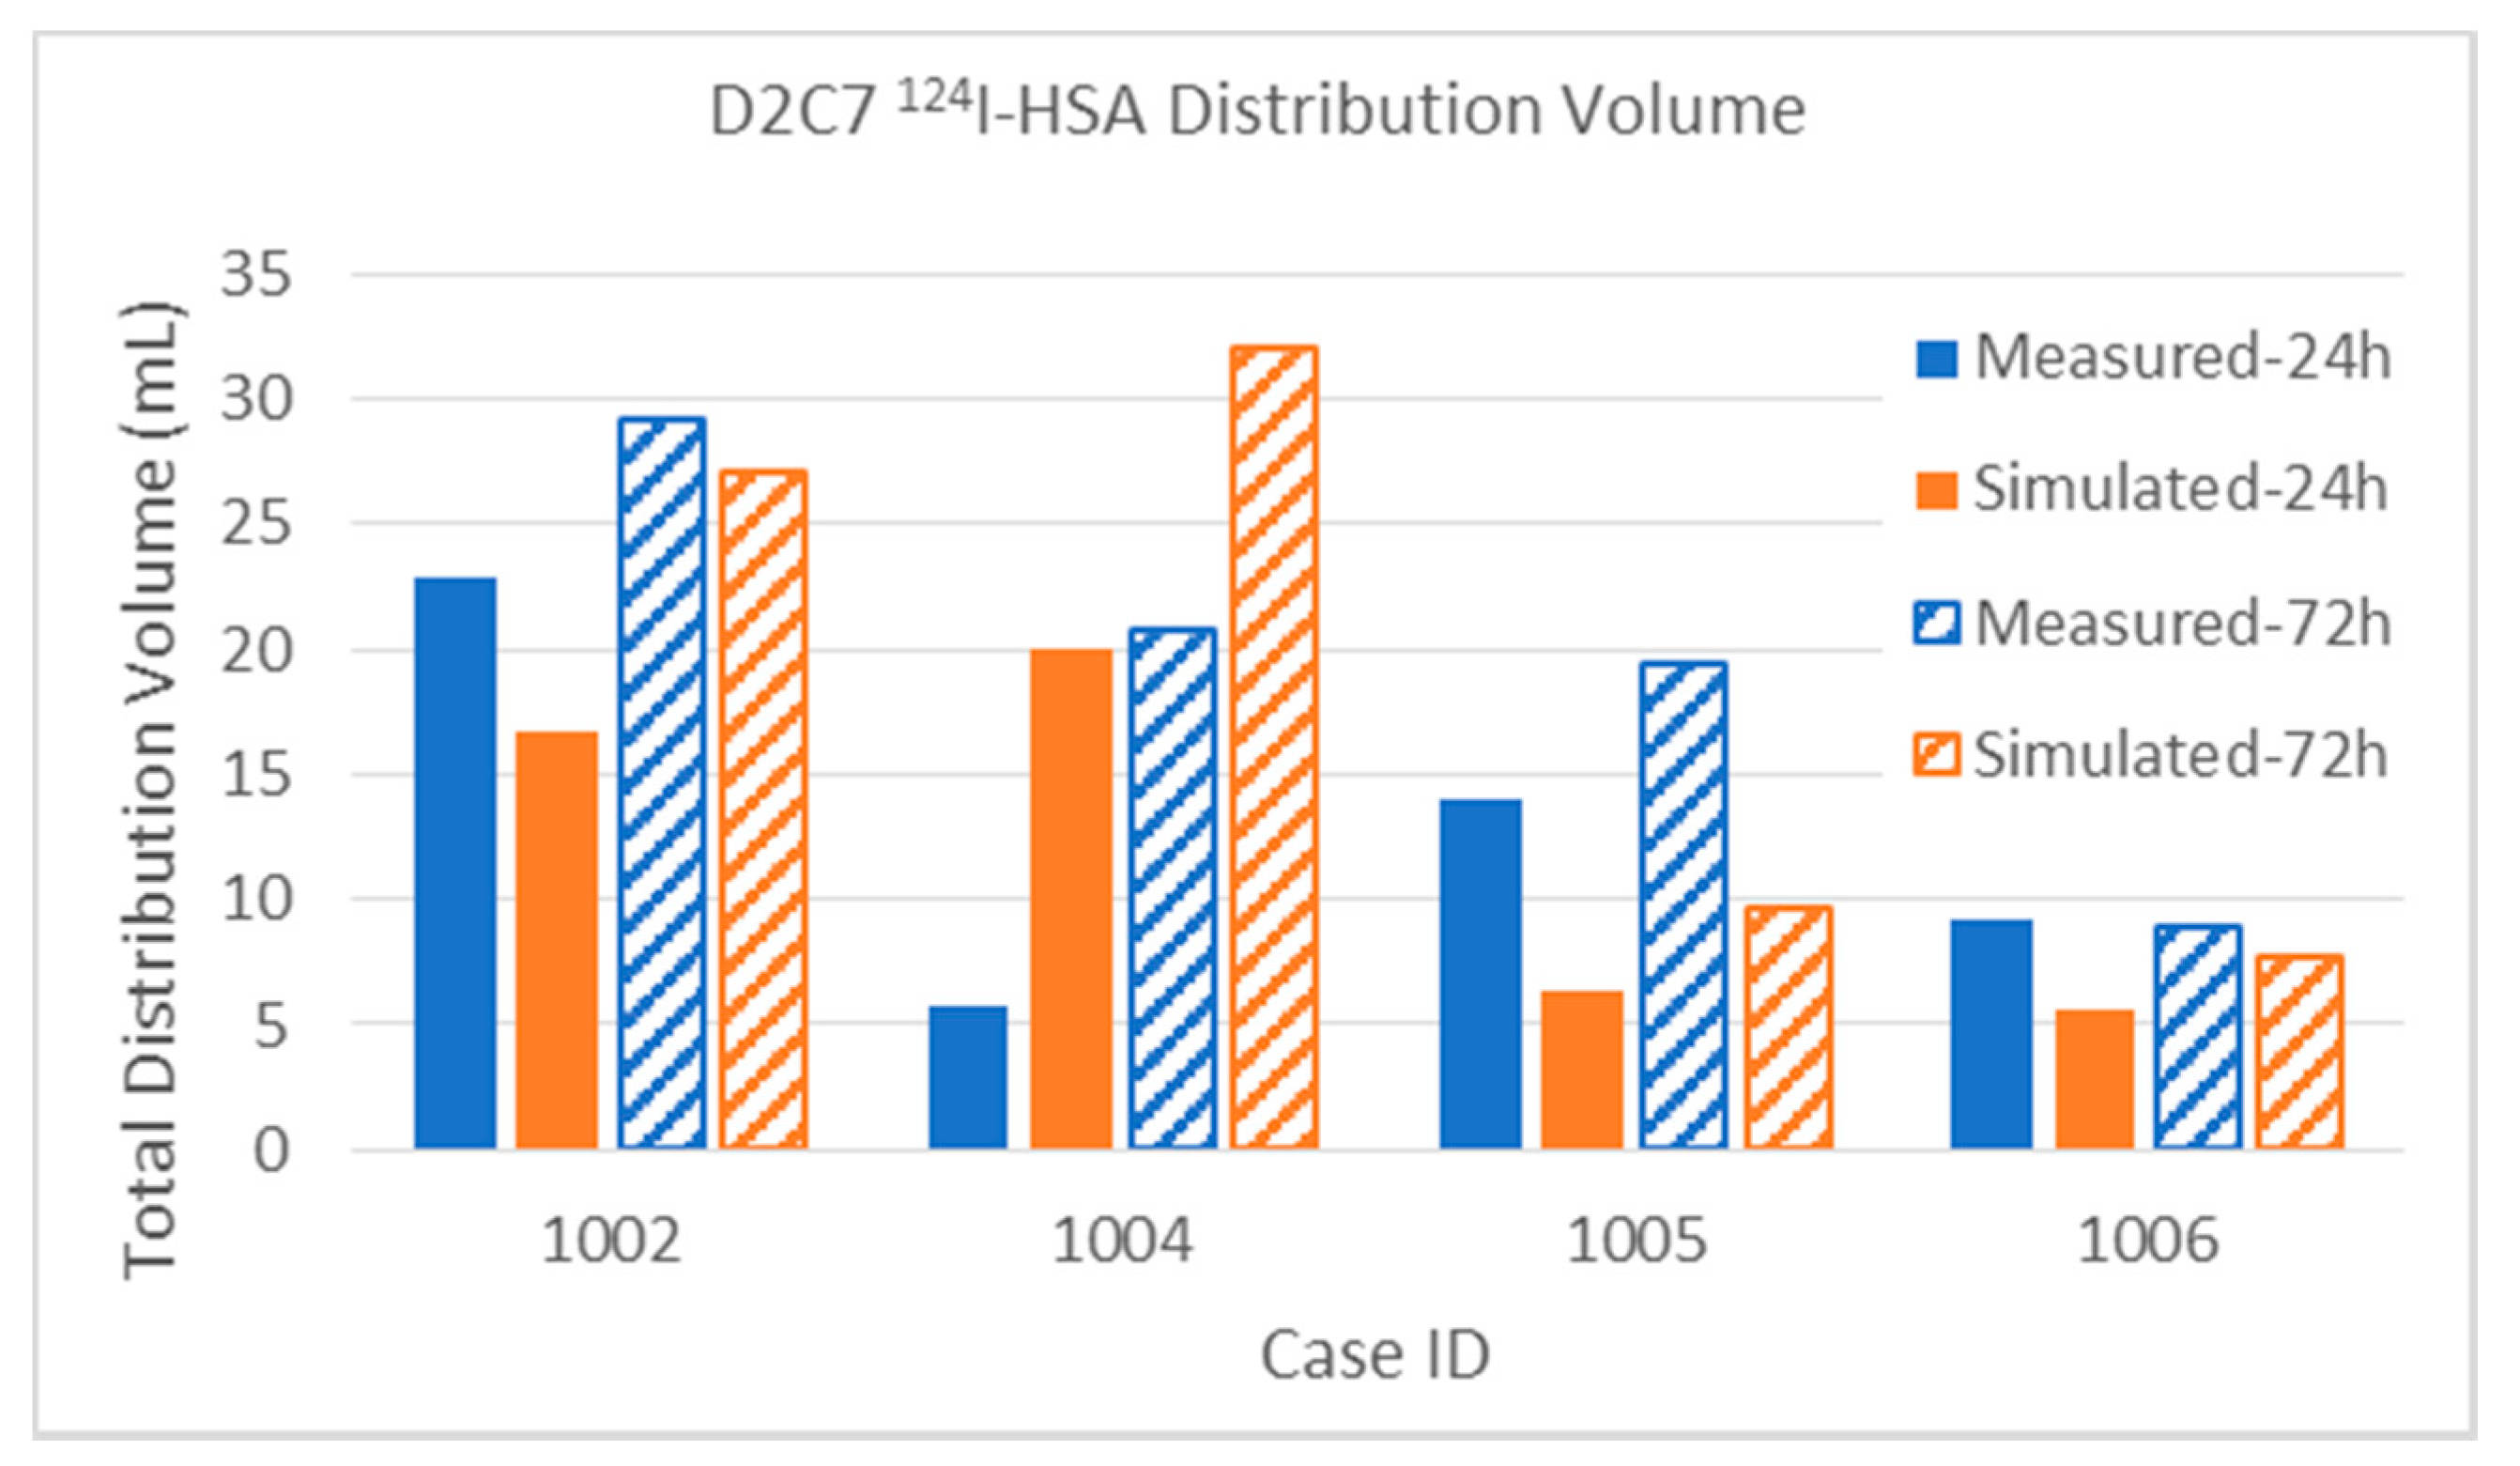

3.2.1. Total Distribution Volume

| 124I | Measured | 4.7 | 3.3 | 18.1 | 25.8 | 22.8 | 29.1 | 47.0% | 33.0% | 21.0% | 30.0% | 10.0 | 86.0 | |

| Simulated | 5.5 | 7.5 | 11.2 | 19.6 | 16.7 | 27.1 | 55.0% | 75.0% | 13.0% | 22.8% | 10.0 | 86.0 | ||

| 124I | Measured | 4.6 | 7.7 | 1.2 | 11.3 | 5.8 | 20.8 | 58.2% | 97.0% | 1.5% | 14.0% | 7.9 | 81.0 | |

| Simulated | 7.4 | 7.4 | 11.3 | 21.9 | 20.0 | 32.0 | 93.0% | 94.1% | 14.0% | 27.0% | 7.9 | 81.0 | ||

| 124I | Measured | 4.9 | 5.0 | 9.1 | 14.4 | 14.0 | 19.4 | 74.2% | 75.8% | 9.5% | 15.0% | 6.6 | 96.0 | |

| Simulated | 2.4 | 2.9 | 3.9 | 6.1 | 6.3 | 9.0 | 36.4% | 43.9% | 4.1% | 6.4% | 6.6 | 96.0 | ||

| 124I | Measured | 4.8 | 4.2 | 3.8 | 4.0 | 9.2 | 8.9 | 57.8% | 50.6% | 4.0% | 4.2% | 8.3 | 94.3 | |

| Simulated | 3.3 | 3.9 | 2.3 | 3.8 | 5.6 | 7.7 | 39.8% | 47.0% | 2.4% | 4.0% | 8.3 | 94.3 | ||